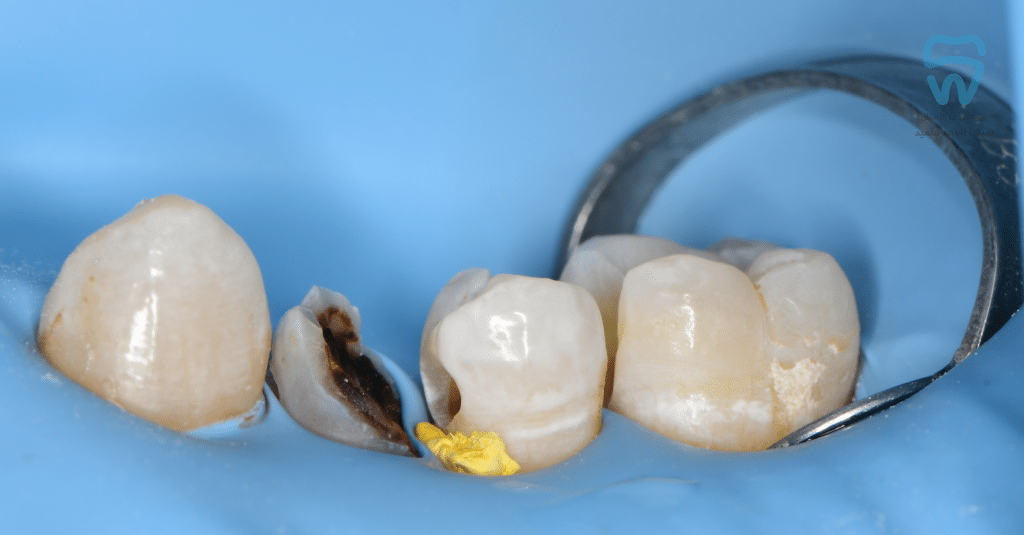

Metal ring of sectional matrix seated with Liquidam

Saddle and sectional bands supported by the modified ring